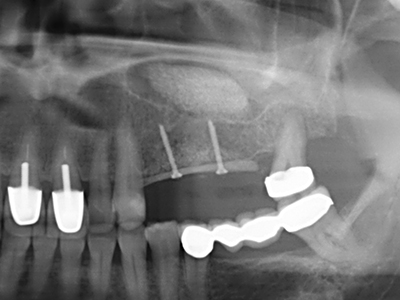

Пиезохирургията има допълнителни предимства при събиране на костни блокове. В допълнение към високата прецизност при остеотомията, описана по-горе, употребата на фините режещи накрайници значително намаляват загубата на материал. Голяма загуба на материал по време на събиране може да се очаква с дебелите накрайници, особено при употреба на борери Линдеман (Lakshmiganthan, Gokulanathan et al. 2012). Базалното разделяне, което е необходимо, особено за присадка на блок при ретромолар, е улеснено от специално създадени правоъгълни триони. В резултат на това, пиезохирургията е разглеждана като прецизна, улеснена и безопасна процедура за събиране на костни блокове в ретромоларното пространство (Happe 2007) (Фиг. 1-12).

Както е показано в миналото, всяка костна хирургия представлява възможна индикация за пиезохирургия. По този начин, за препарацията на подвижни сегменти в остеогенеза (Фиг. 23-25) и остеотомия се използват специални накрайници, без да се застрашава снабдяването с кръв в кресталната зона, което е от съществено значение за успеха и на двете техники (Gonzalez-Garcia, Diniz-Freitas et al. 2008).